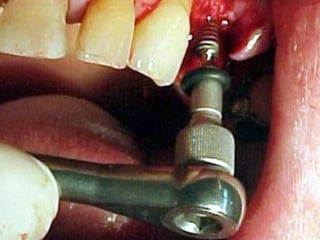

Primer tiempo quirúrgico; Exposición del maxilar para tomar una impresión del

hueso y poder elaborar la estructura implantaria.

Primer tiempo quirúrgico;Exposición del maxilar para tomar una impresión del hueso y poder elaborar la estructura implantaria.

Exposición del maxilarpara tomar la impresión

Previamente se haelaborado un portaimpresiones en acrílico de autopolimerización, el cual será llenado con silicona para obtener el duplicado de la estructura ósea.